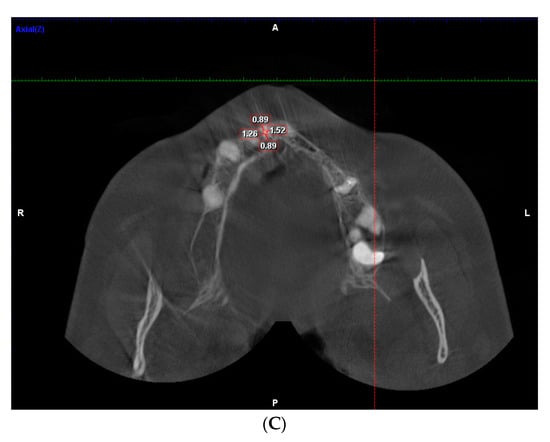

2. Materials and Methods

3.3. Dentinal Thickness in Apical Part